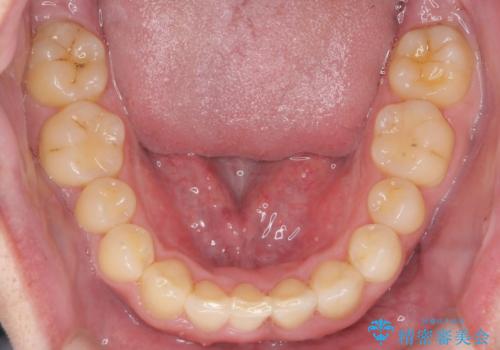

前歯のすき間 歯のがたつき

- 前歯のすき間とがたつきを主訴に来院。

右上の前歯は過去にがたつきがあったとのことで抜いてしまっていました。

歯の数を合わせるために、下の歯を1本抜いて矯正しています。

下の前歯を抜歯したことでブラックトライアングルができましたが、仕上げにIPRを加えることで目立たなくすることができました。